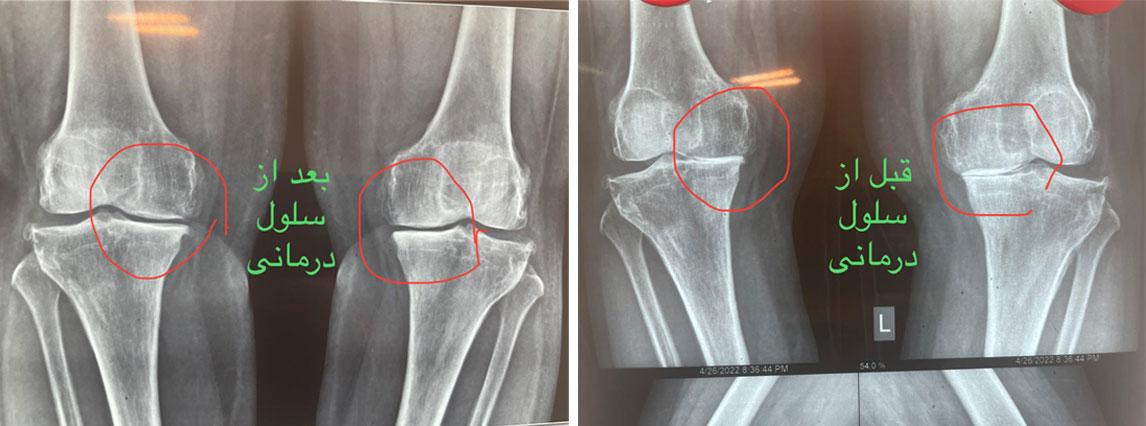

تکنولوژیهای درمانی نوینی مانند سلولدرمانی با بهرهگیری از سلولهای بنیادی، چشماندازهای جدیدی برای بازسازی آسیبهای مفصل زانو به وجود آوردهاند.

در این روش، سلولهای بنیادی، که از منابعی چون مغز استخوان یا بافت چربی بیمار استخراج شدهاند، جدا و تکثیر میشوند. سپس این سلولها به داخل مفصل زانو تزریق میشوند.

این سلولهای بنیادی دارای توانایی ترمیم بافتهای آسیبدیده مفصل، از جمله غضروف، رباط و منیسک هستند. علاوه بر این، آنها به کاهش التهاب، احیای سلولهای مفصلی، و در نهایت بهبود عملکرد مفصل منجر میشوند.

مطالعات نشان دادهاند که سلولدرمانی میتواند به بهبود درد مفصل، افزایش دامنه حرکتی، و بهبود کیفیت زندگی بیماران مبتلا به آرتریت و آسیبهای مفصل زانو کمک موثری نماید.

ولی جدیدترین روشی که امروزه در تمام دنیا برای درمان ارتروز و ساییدگی زانو و ستون فقرات استفاده میشود تزریق مستقیم سلولهای بنیادی داخل زانو یا ستون فقرات یا همان سلول درمانی است . مزیت سلول درمانی نسبت به روشهای پیشین از جمله تزریق ازن یا پی آر پی اینست که این روشها بیشتر برای مفصل حالت تسکین ایجاد میکنند و در واقع مسکن هستند در حالیکه سلول درمانی منجر به تشکیل غضروف در مفصل شده و از طریق ایجاد غضروف درد را از بین میبرد .